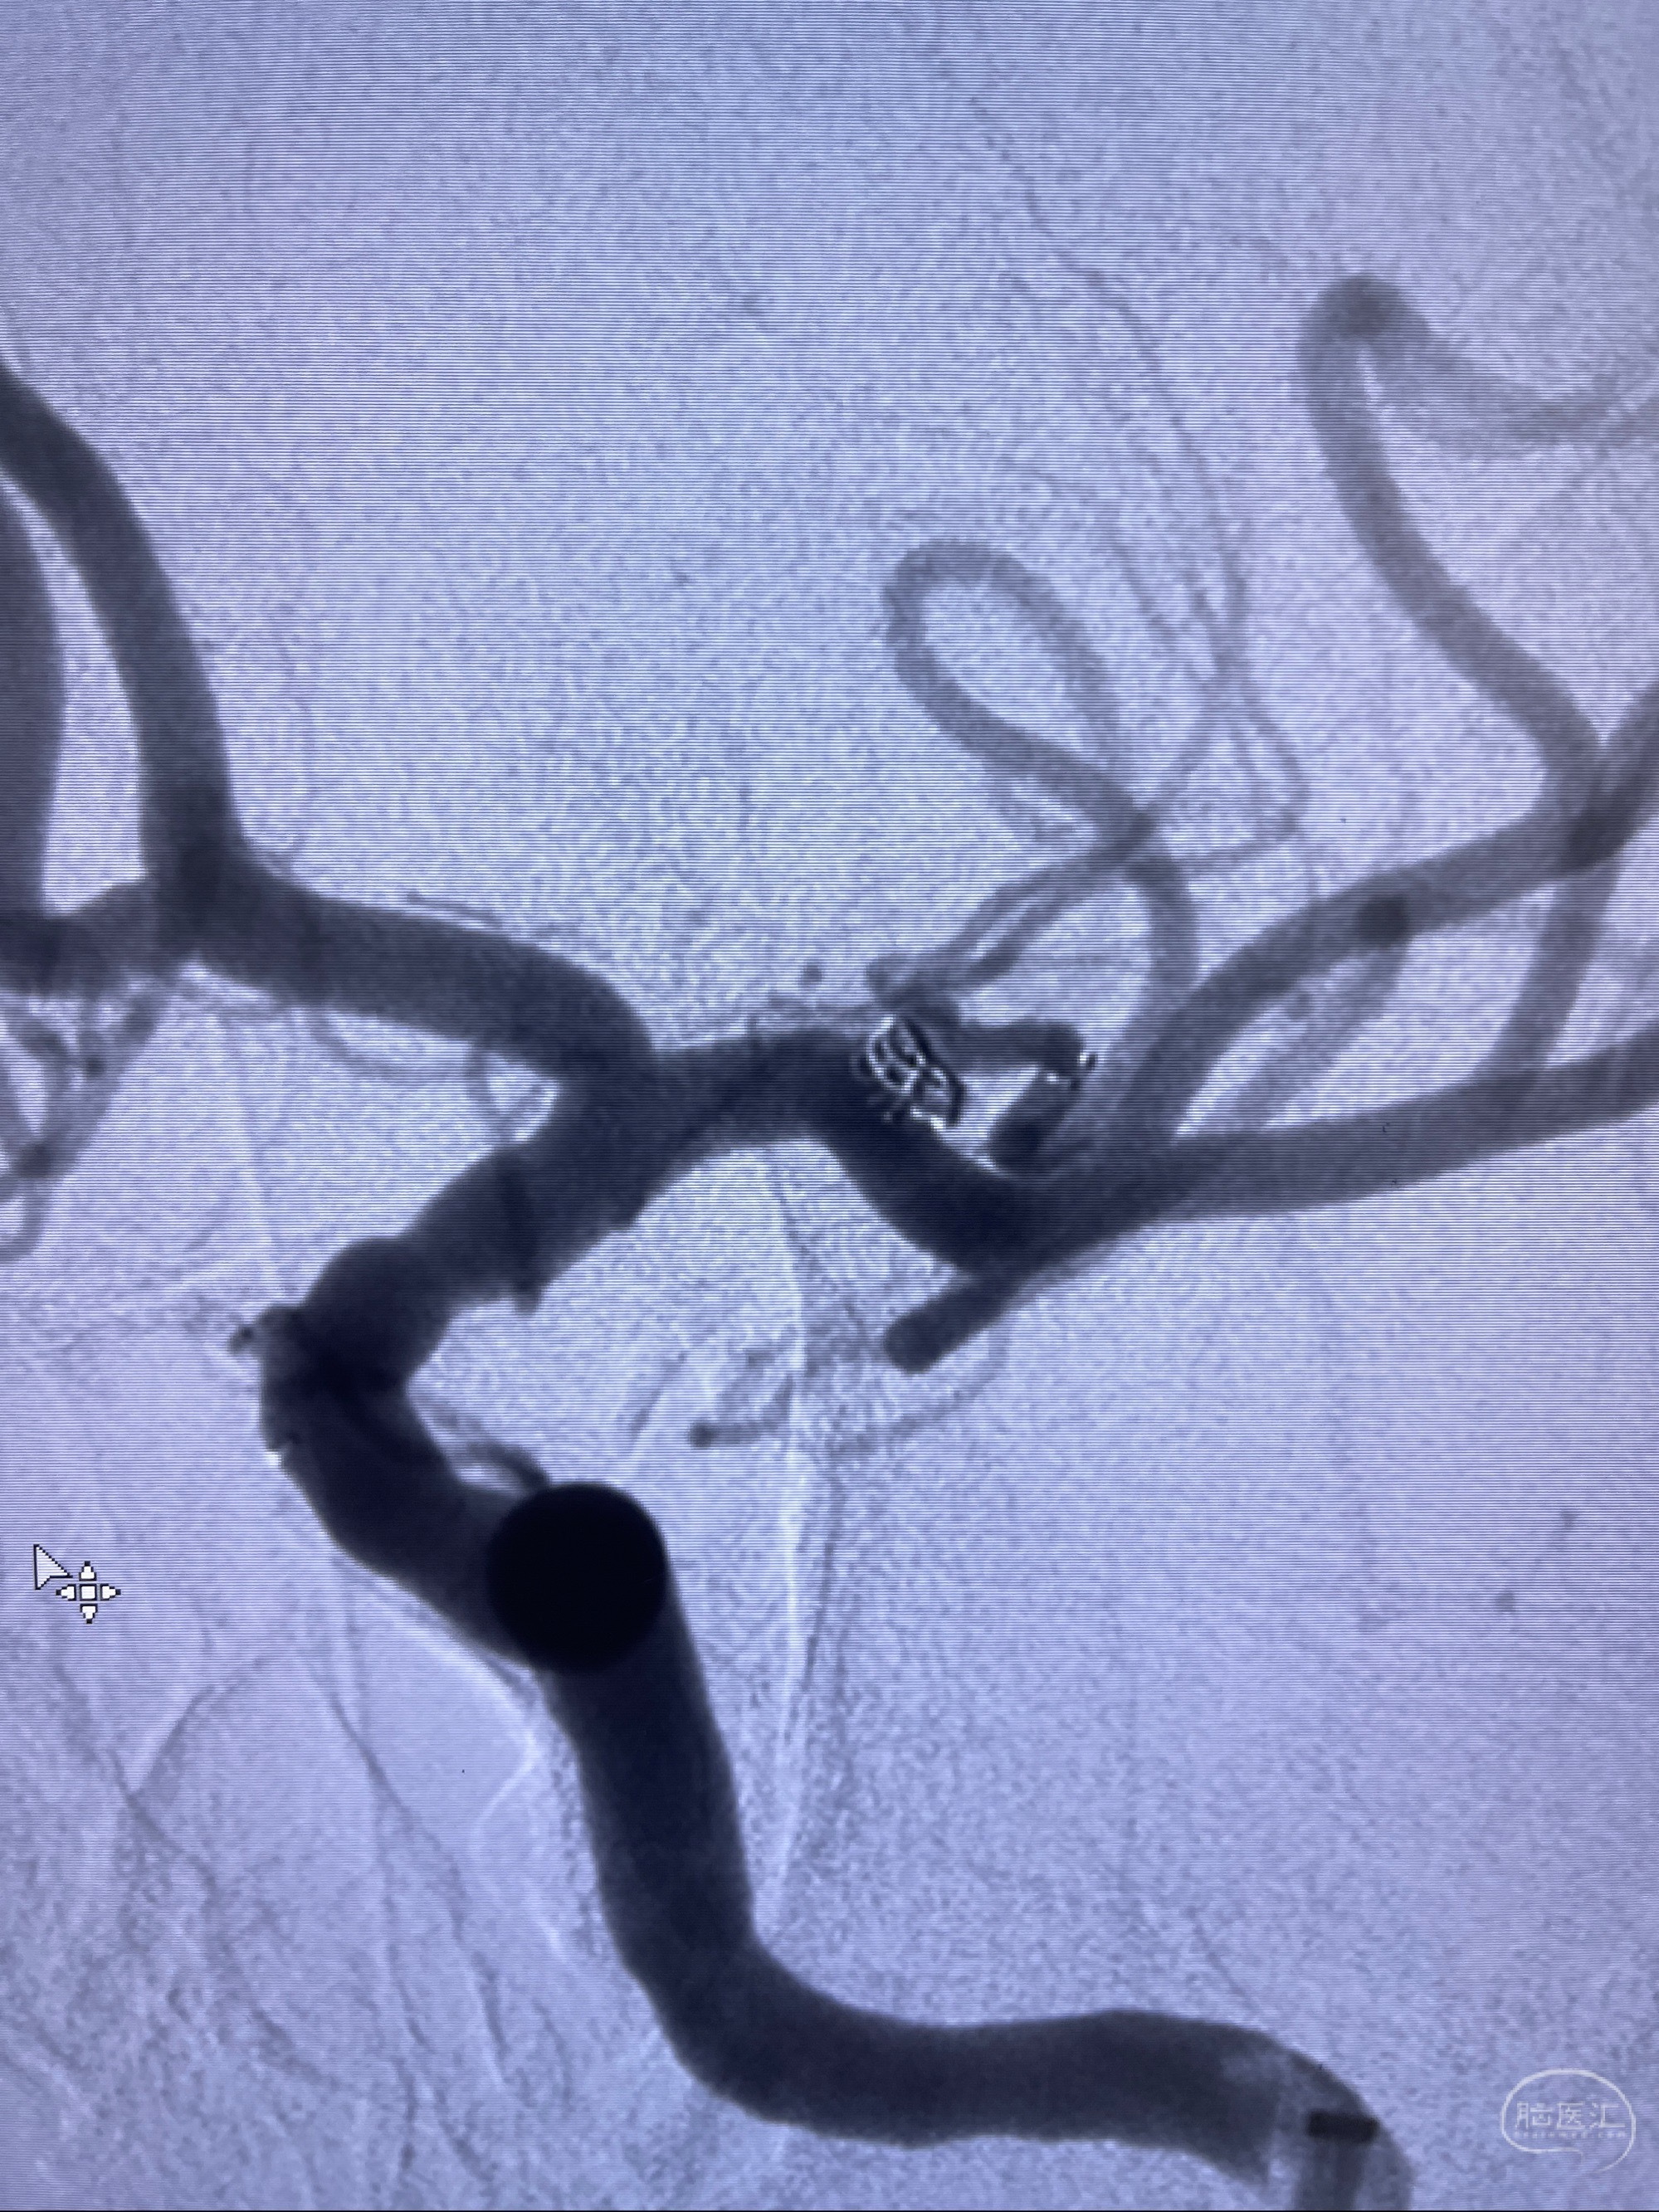

2023-08-14DSA:

左侧大脑中动脉动脉瘤,约2.6-2.8-3.4-2mm大小(瘤颈部、瘤体部、瘤高)

1.左侧大脑中动脉动脉瘤,约2.6-2.8-3.4-2mm大小(瘤颈部、瘤体部、瘤高)